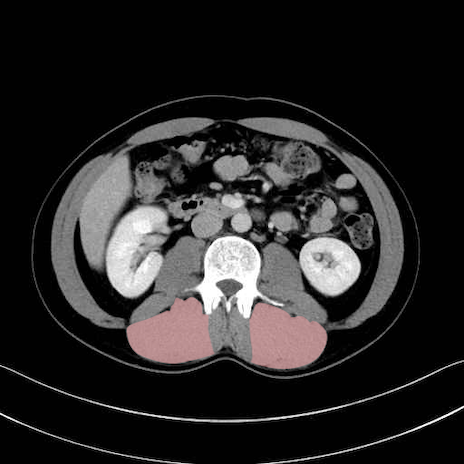

脊柱起立筋 (Erector spinae)

多裂筋 (Multifidus)